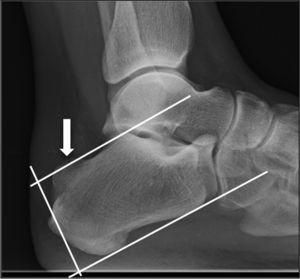

- Las imágenes radiográficas por Rayos X - "son de gran ayuda a la hora de clasificar esta patología y diagnosticar el tratamiento apropiado"-